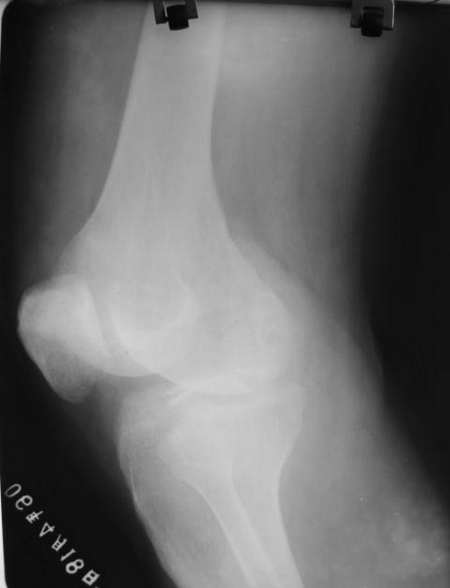

侧位片股骨远端与髌骨重叠部见团块壮骨密度影,考虑股骨远端撕脱骨折

片的质量不是很好,髌骨前下角好像有透亮线?

关节积液及股骨远端可疑骨折

左胫骨髁间隆突骨折,建议ct检查!!

____关节囊内积血!!!